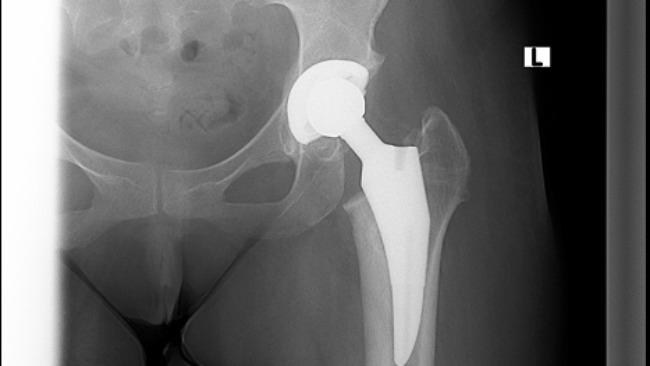

Witam, nazywam się Magdalena i mam 32 lata. Moje problemy zdrowotne zaczęły się już w wieku 4 lat gdzie w wyniku pękniętego wyrostka dostałam sepsy. Nie dawano mi szans na przeżycie ale się udało. Później doszły alergie i również astma oskrzelowa. Najgorsze zaczęło się w wieku 12 lat zaczęłam coraz bardziej utykać i zdiagnozowano u mnie złuszczenie głowy kości udowej lewej,noga była krótsza o kilka cm. Leczenie które u mnie zastosowano to zespolenie kości udowej za pomocą śruby kaniulowanej. Moje biodro zostało unieruchomione co utrudniało mi codzienne życie. Siedzenie czy nawet zawiązanie buta było dla mnie ogromnym wyzwaniem. Noga po mimo leczenia coraz bardziej skręcała się do wewnętrznej strony. W wieku 18 lat przeszłam operację usunięcia woreczka żółciowego który wysiadł mi w wyniku zażywania leków przeciwbólowych. Również w wieku 18 lat śruba z biodra została usunięta. Później dowiedziałam się że muszę przejść operację wstawienia endoprotezy biodrowej. W kolejce czekałam aż 5 lat gdzie stan mojej nogi uległ pogorszeniu, moja kość biodrowa była praktycznie starta do zera. Po operacji endoprotezy biodra ciężko do siebie dochodziłam. Po wybudzeniu nie miałam czucia w nodze co utrzymywało się prawie przez pół roku.Po operacji moja noga na odcinku udowym została wyprostowana ale od kolana w dół była dalej skręcona do środka. Lekarz zalecił kolejną operację jaką było wyprostowanie nogi poniżej kolana. Na operację czekałam kolejne 2 lata. Niestety operację przeszłam fatalnie, noga zaczęła bardzo puchnąc, pani która ściągała szwy zignorowała to, co skutkowało tym, że miałam głębokie otwarte rany. Codziennie musiałam przyjeżdżać do szpitala na założenie plastrów które zespajały otwartą ranę. Noga była tak spuchnięta że moja stopa dosłownie była czarna. Lekarz zalecił na "Cito" wizytę u chirurga naczyniowego ale lekarz bo badaniu usg nic nie stwierdził. Rany po mimo braku infekcji ciężko się goiły. Lekarz stwierdził że pewnie mój organizm próbuje odrzucić ciało obce z organizmu więc stąd te dolegliwości.W kolejnych latach usunięto mi wszystkie gwoździe z kości piszczelowej. Niestety problem z brakiem czucia w nodze a jednoczesnym bólem nie został rozwiązany. Noga dalej była mocno spuchnięta więc lekarz zalecił kolejną wizytę u chirurga naczyniowego ale i tu nie stwierdzono przyczyny a jedynie przypuszczenie że być może naczynia limfatyczne zostały uszkodzone. I tak zostałam bez żadnej diagnozy i leczenia. Próby leczenia w innych placówkach się nie udały bo każdy lekarz mówił że mam sobie iść do lekarza który mnie operował bo oni po kimś robić nie będą. Mój stan teraz jest kiepski, nie tylko noga jest bardzo spuchnięta, jest dwa razy większa od prawej nogi, ale puchnie mi cała lewa strona ciała. Mój kręgosłup który się skrzywił przez to ,że przez tyle lat chodziłam o krótszej nodze również mocno daje o sobie znać, ból często jest nie do zniesienia, czasami nawet promieniuje do klatki piersiowej co jest najbardziej bolesne. Za kilka lat znowu muszę przejść operację wymiany endoprotezy która starcza na około 10 lat. Nie posiadam prawa do renty dlatego, że dyrekcja szkoły powiedziała w prost ,że jeżeli będę uznana za osobę niepełnosprawną to nie mam prawa uczyć się placówce która nie jest dostosowana, nawet nie miałam prawa wejść na teren szkoły o kulach a w tamtych czasach nie było takiej szkoły w pobliżu mojego miasta więc renta przepadła. Od MOPSu też nie dostałam żadnej pomocy. Boję się o swoją przyszłość. Wiem, że jestem dużym obciążeniem dla moich rodziców,moja psychika jest na wykończeniu dlatego zwracam się z prośbą o wsparcie do państwa. Zebrane pieniądze przeznaczyłabym na leczenie,usamodzielnienie się i na życie.